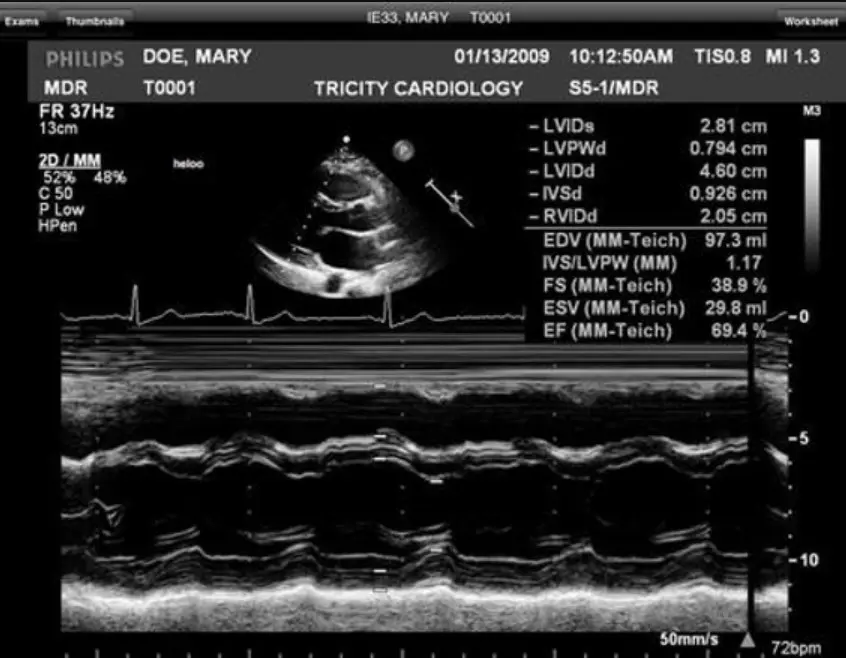

The software excels in medical imaging, supporting a wide range of modalities, including echocardiograms, vascular studies, and general ultrasound. UltraLinq allows healthcare providers to view, annotate, and analyze images directly within the platform, facilitating precise diagnoses and informed treatment plans. The platform’s customizable reporting tools further streamline clinical workflows, enabling the creation of detailed, specialty-specific reports tailored to the unique needs of each practice.